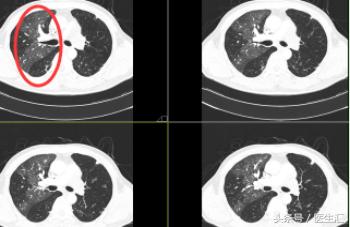

CT 图片示:

患者右肺肺野密度不对称,左肺尚可,出现的是 “马赛克征”。可考虑:小气道病变或肺栓塞。

P.S :“马赛克”征是肺小气道病变时高分辨力CT或薄层CT所示的一种非特异性征象。表现为肺密度不均匀,补丁状的异常透光区+斑片状的磨玻璃密度影镶嵌存在,形似“马赛克”。

住院期间患者反复高热,CT提示左肺空洞。